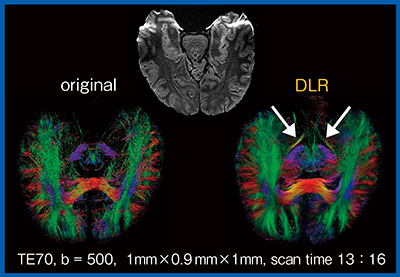

高分解能whole brain DTIカラーマップでは,DLR処理によってノイズが除去されたことで,髄枝の描出や構造の分離が明瞭となる。また,高分解能DWIから作成したトラクトグラフィは,DLR処理によって神経線維が明瞭となり,オリジナル画像では不明瞭だった視索(↓)も良好に描出されている(図4)。

図4 拡散テンソルトラクトグラフィにおけるDLRの効果